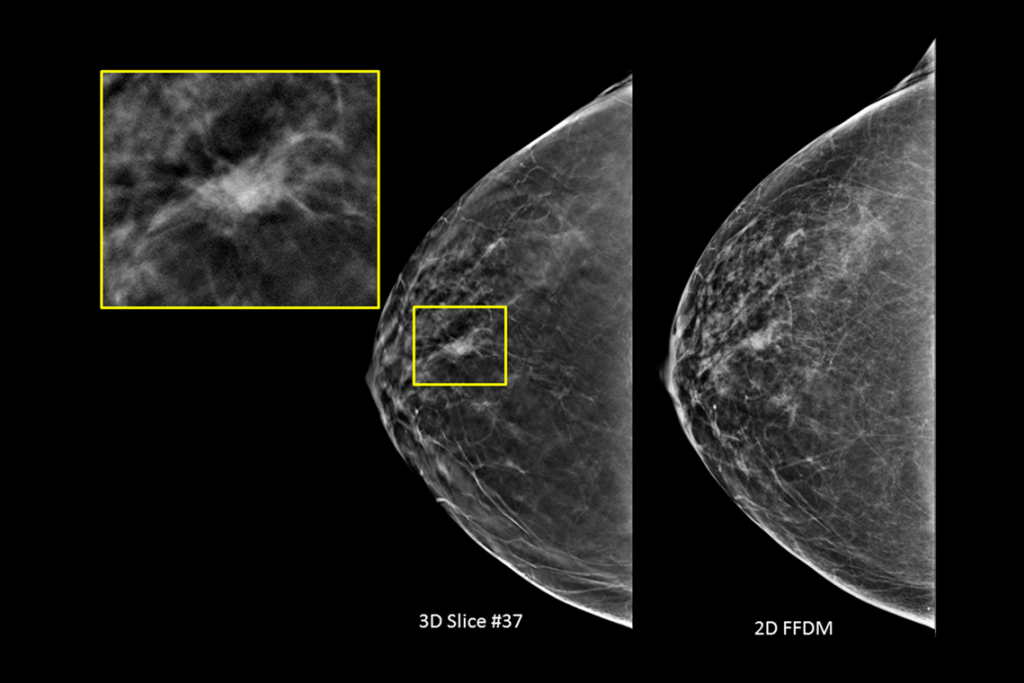

Kliniske billeder fra mammografi af et bryst med en mistænkelig læsion